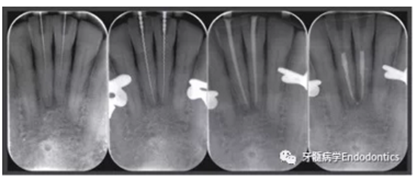

在患者下頜牙上試戴導(dǎo)板(帶有專門制作的金屬袖,steco-system-technik GmbH & Co. KG, Hamburg, Germany) ,判斷是否合適(圖7)。通過導(dǎo)板可以定位根管入路點(diǎn),并微創(chuàng)去除牙釉質(zhì),直到牙本質(zhì)暴露。鉆針轉(zhuǎn)速設(shè)定為10000RPM,上下提拉鉆頭獲得根管根尖1/3的入路(圖8)。當(dāng)鉆針柄接觸導(dǎo)板上的金屬袖時(shí),鉆針尖端到達(dá)目標(biāo)位點(diǎn)。整個(gè)根尖入路的制備過程耗時(shí)約10分鐘。圖9展示了微創(chuàng)預(yù)備的根管入路。然后進(jìn)行常規(guī)的根管治療。用1%的次氯酸鈉沖洗根管,單支往返銼(R25, VDW, Munich, Germany)預(yù)備根管,超聲蕩洗,干燥根管后用氫氧化鈣(Ultracal XS, Ultradent Products Inc, South Jordan, UT, USA) 封藥,暫封(CavitTM, 3 M ESPE) 。兩周后,患牙均無叩痛,使用熱牙膠垂直加壓技術(shù)和環(huán)氧樹脂糊劑(AH Plus, De Trey, Konstanz, Germany)充填根管。圖10為根管治療過程中拍攝的x線片。髓腔清理后,使用復(fù)合樹脂(Filtek Supreme XTE, 3 M ESPE, Seefeld,Germany) 和多步法粘接劑(Optibond FL, Kerr, Orange, CA, USA).充填。

圖10.根管治療過程中拍攝的X線片。(a)微創(chuàng)根管入路制備完成拍攝的定位片,(b)根管長(zhǎng)度測(cè)量,(c)試主尖片,(d)去除冠方根充填物后的最終根充效果。